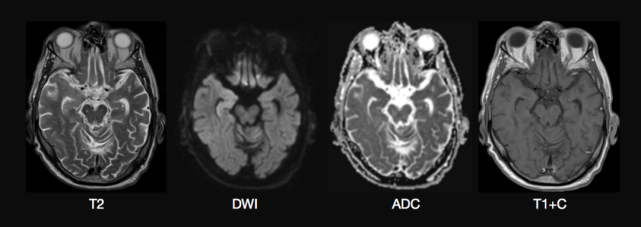

图 癫痫持续状态患者右侧丘脑和海马MRI上异常信号

55岁男性因发热伴癫痫持续状态入院,头颅MRI可见右侧颞叶内侧有轻微的T2 高信号,累及海马并延伸至右侧丘脑,伴弥散受限,病灶无增强,可能与癫痫持续状态有关(Katramados A M, et al. Epilepsia, 2009, 50(2): 265-275.)。